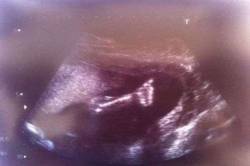

Жизнеутверждающее послание из утробы матери (3 фото)

Ещё нерождённой малышке врачи поставили страшный диагноз – гипоплазия левых отделов сердца – который практически не оставлял ей шансов на выживание. Родителям, Фей и Майклу Мэрриш (Fay & Michael Murrish), дважды предлагали прервать беременность, но в очередной раз пойдя на обследование УЗИ и увидев снимок, они больше не сомневались в своём правильном решении…...